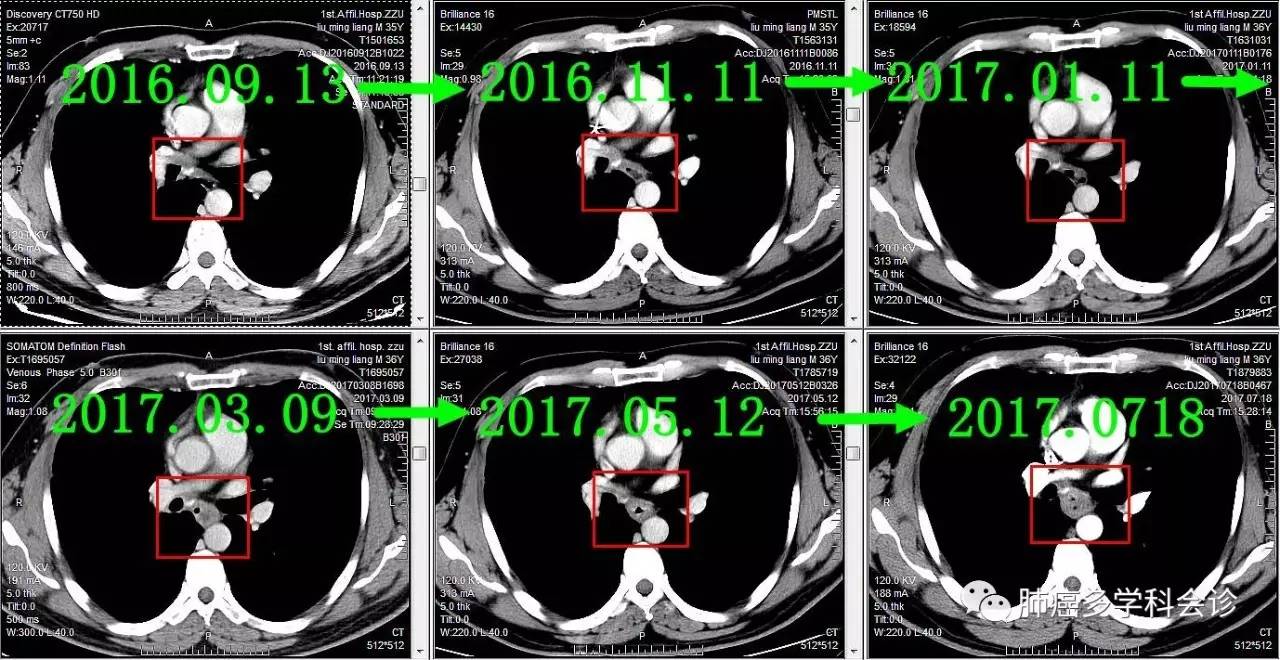

食管转移灶从小到大

下面着重展示食管转移灶的发展过程。从2016-09-13(完成2个周期化疗)开始,上下两图分别为各时间点CT的上下两层:

食管不是肺癌的常见转移部位,容易被忽视。回顾该患者以往的胸部 CT 可见:在纵隔淋巴和原发灶逐渐畏缩过程中,食管转移却逆势发展起来,反映了肿瘤对治疗反应的异质性。